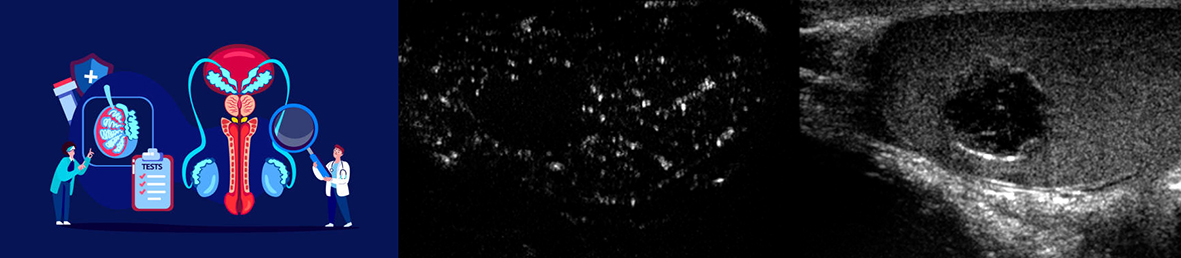

Un elemento distintivo del laboratorio è rappresentato dallo sviluppo e dall’applicazione della diagnostica ecografica avanzata nello studio delle patologie testicolari e scrotali. In particolare, il gruppo si occupa di ecografia ad alta risoluzione, Doppler avanzato e tecniche di contrast-enhanced ultrasound (CEUS), integrando l’analisi qualitativa con approcci quantitativi innovativi, inclusi modelli di analisi delle immagini e radiomics, finalizzati a migliorare l’accuratezza diagnostica e supportare le decisioni cliniche nei contesti più complessi, come le lesioni testicolari indeterminate.

| Philips Affiniti 30 | Ecografo |